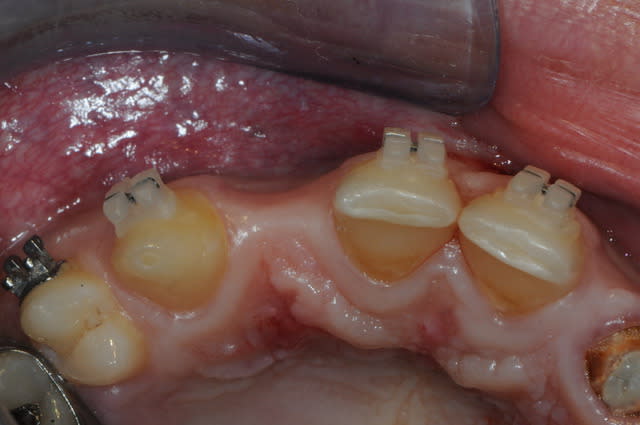

Voici le cas d'une jeune patiente de 16 ans qui présente une agénésie et qui est en attente d'implants différés à la fin de croissance.

En attendant, je me tâte un peu sur la temporisation, car on a des surfaces de collages très confortables sans interférences avec l'occlusion (cf photo, zone hachurée), et je suis très réticent à esquinter les quenottes toutes neuves de l'angelot pour coller un maryland et le recoller et le recoller et le recoller, etc...